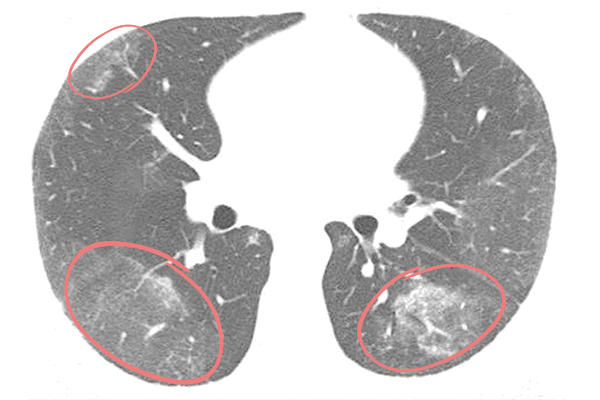

Посттрансплантационная лимфопролиферативная болезнь на рентгенограмме, КТ органов грудной клетки

Лимфома легких на КТ

Признаки лимфомы легких особенно выражены на четвертой стадии заболевания, когда болезнь поражает дыхательный орган. На КТ при этом будут видны увеличенные лимфоузлы, формирующие цепочки, конгломераты. При этом у пациента может также наблюдаться отек легких. Однако высокая разрешающая способность КТ позволяет выявить лимфому на ранней, первой стадии.

На КТ лимфомы, как и любые уплотнения, визуализируются сравнительно более светлым цветом. В норме воздушная легочная паренхима практически однородного темного цвета. Иногда таких уплотнений несколько и они диссеминированны. Контуры лимфомы четкие и ровные. Вокруг патологических очагов обнаруживаются участки «матового стекла».